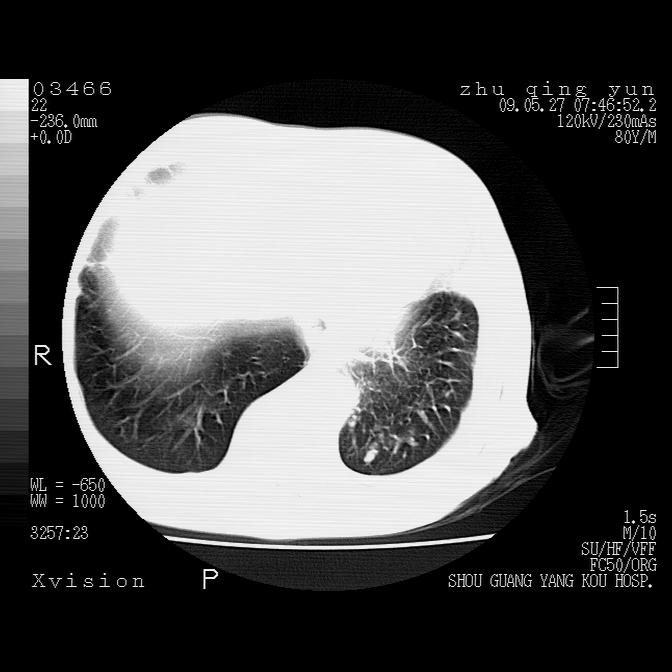

病人男性,年龄80,气喘来院,其他病史不太详细,1月前有过恶心,呕吐,在当地人民医院做过钡餐,诊断胃炎,

1)考虑左肺中央型肺癌并阻塞性肺炎,后下纵隔受侵伴纵隔淋巴结转移。2)双侧少量胸腔积液,胸膜增厚。3)心包积液。

左肺下叶见多发片状及结节状病灶,左肺基底段支气管闭塞,纵隔内见多发淋巴结肿大,纵隔向左侧移位,左侧胸廓变小。应该是左肺下叶中心型肺癌,纵隔淋巴结转移,左侧肺内转移,左肺基底段肺不张,阻塞性肺炎。

1)考虑左肺中央型肺癌并左肺下叶阻塞性肺炎、不张;左胸膜腔积液、心包积液、纵隔淋巴结转移;癌肿累及左心房。2)左心室大。冠状动脉壁钙化斑。

支持以上,左肺肿块应该是周围型吧,考虑左下肺周围型肺癌伴肺内转移,阻塞性肺炎,纵隔淋巴转移,左侧胸膜及心包转移